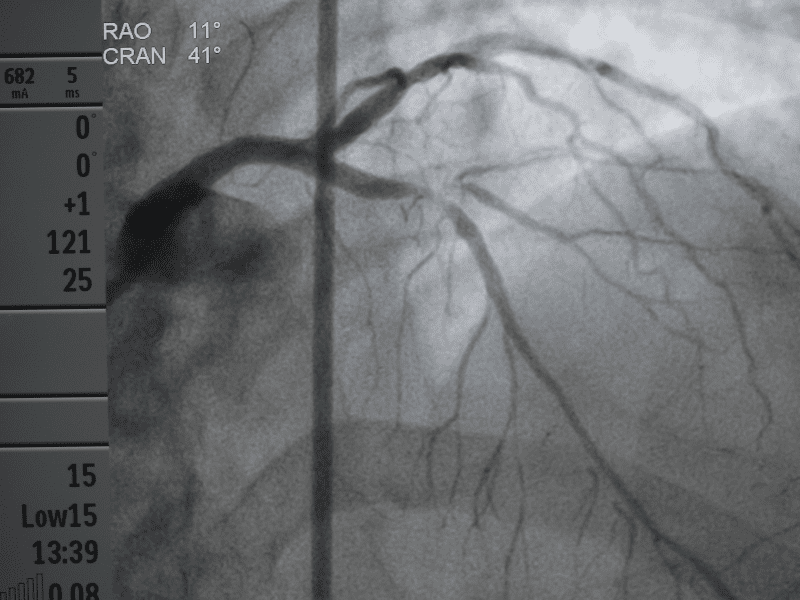

- Angioplastica: Un intervento minimamente invasivo per dilatare le arterie ristrette, ripristinando il flusso sanguigno.

- Bypass arterioso: Nei casi più gravi, un intervento chirurgico per creare una nuova via per il flusso sanguigno, bypassando le arterie ostruite.